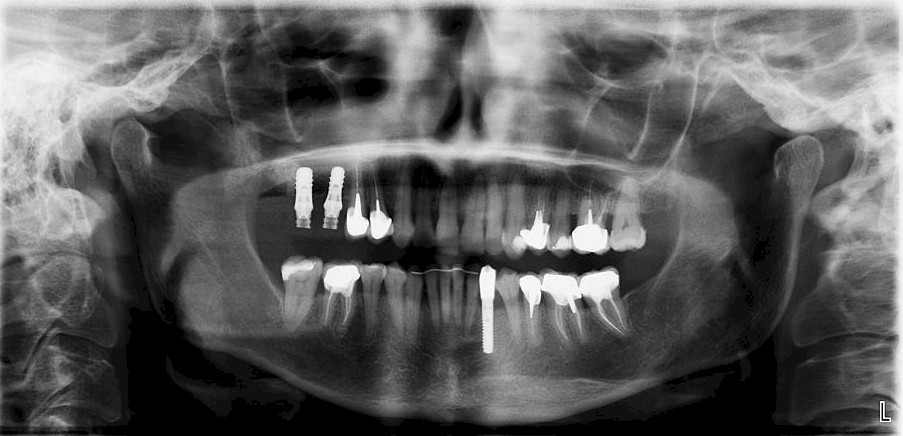

L’orthodontiste doit travailler en collaboration avec une équipe d’autres spécialistes pour définir un calendrier thérapeutique et donner au patient adulte le meilleur résultat.

- Intégrer la réalisation des prothèses et des implants

- Déterminer les cas nécessitant une intervention chirurgicale orthognathique.

- Diagnostiquer le dysfonctionnement de l’articulation temporo-mandibulaire (douleur de la mâchoire) avant, pendant ou après la dent mouvement.

- Prendre en compte le contexte médical des Apnée du Sommeil